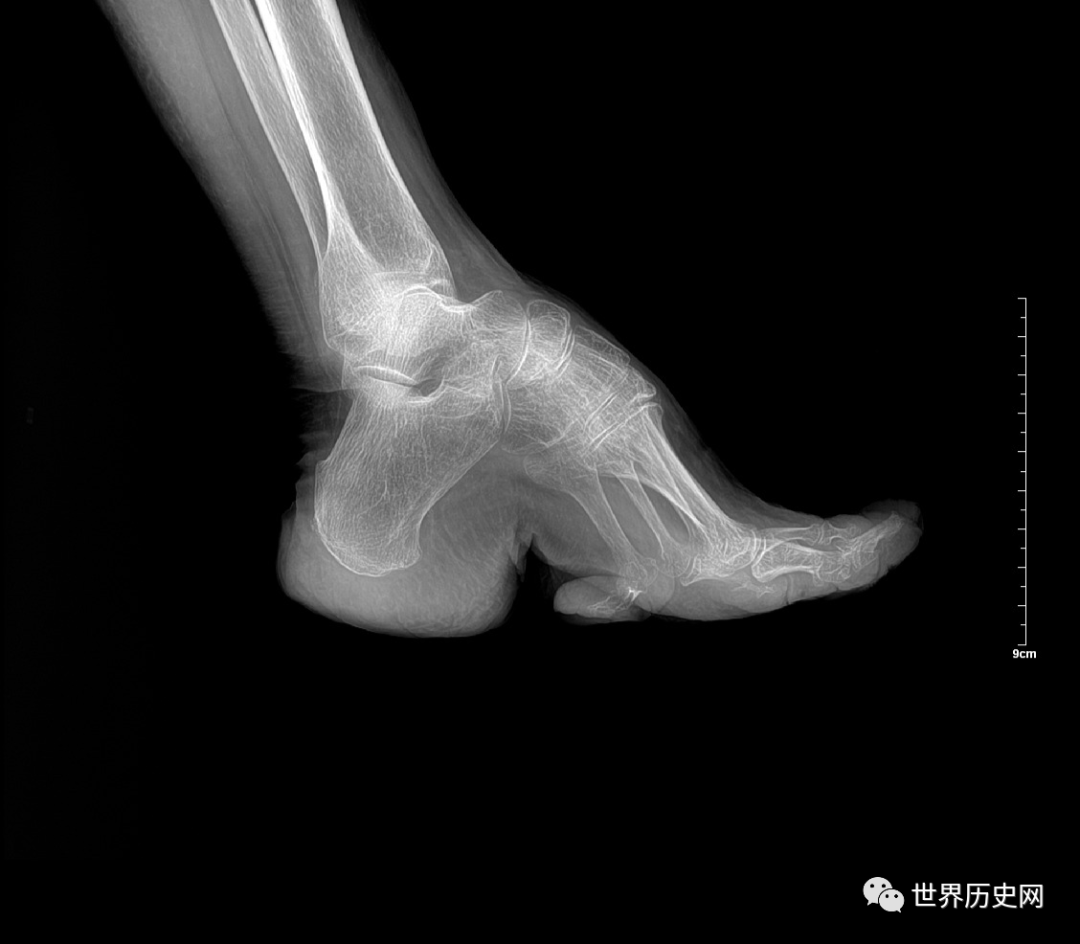

而裹脚的目的,就是为了限制脚的发育,让脚背弯曲,女子一般从幼年时期学会走路时,就要开始裹脚。因为幼年时期的女孩,骨骼才开始发育,骨头比较软,尚未定型,是最适合裹脚的时期。

裹脚的方式看似简单,但却十分残忍,是硬生生将骨头掰断,女性在这个过程中,不仅仅要承受剧烈的疼痛,在此之后还要面临诱发炎症的风险。